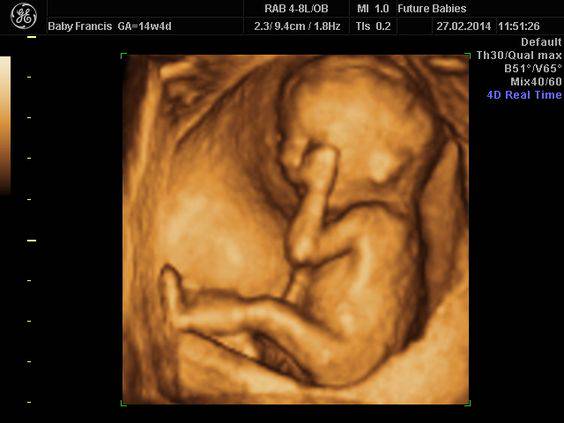

高層次超音波是一種針對胎兒進行非常詳細且全面性結構檢查的2D超音波檢查,檢查時間約30至60分鐘,比一般例行產檢所用的超音波時間長,檢查範圍涵蓋胎兒從頭到腳的各個器官與外觀,包括腦部、眼睛、耳朵、心臟、腸胃、腎臟、四肢骨骼及手指腳趾等,並同時測量子宮頸長度、臍帶血流等相關指標。

與一般產檢中使用的第一級超音波(主要檢查胎位、胎兒大小、羊水量)不同,高層次超音波屬於更高解析度的檢查,能夠檢測胎兒是否有結構異常,例如脣顎裂、心室中隔缺損等先天性缺陷。此檢查並非針對染色體異常(如羊膜穿刺或基因晶片檢查),而是針對胎兒器官結構的完整性做評估。

建議在懷孕20至24週時進行高層次超音波,這時期能提供胎兒第一次全面的健康狀況評估,讓準父母及早了解胎兒發育狀況,若有異常也能及早追蹤與處理。